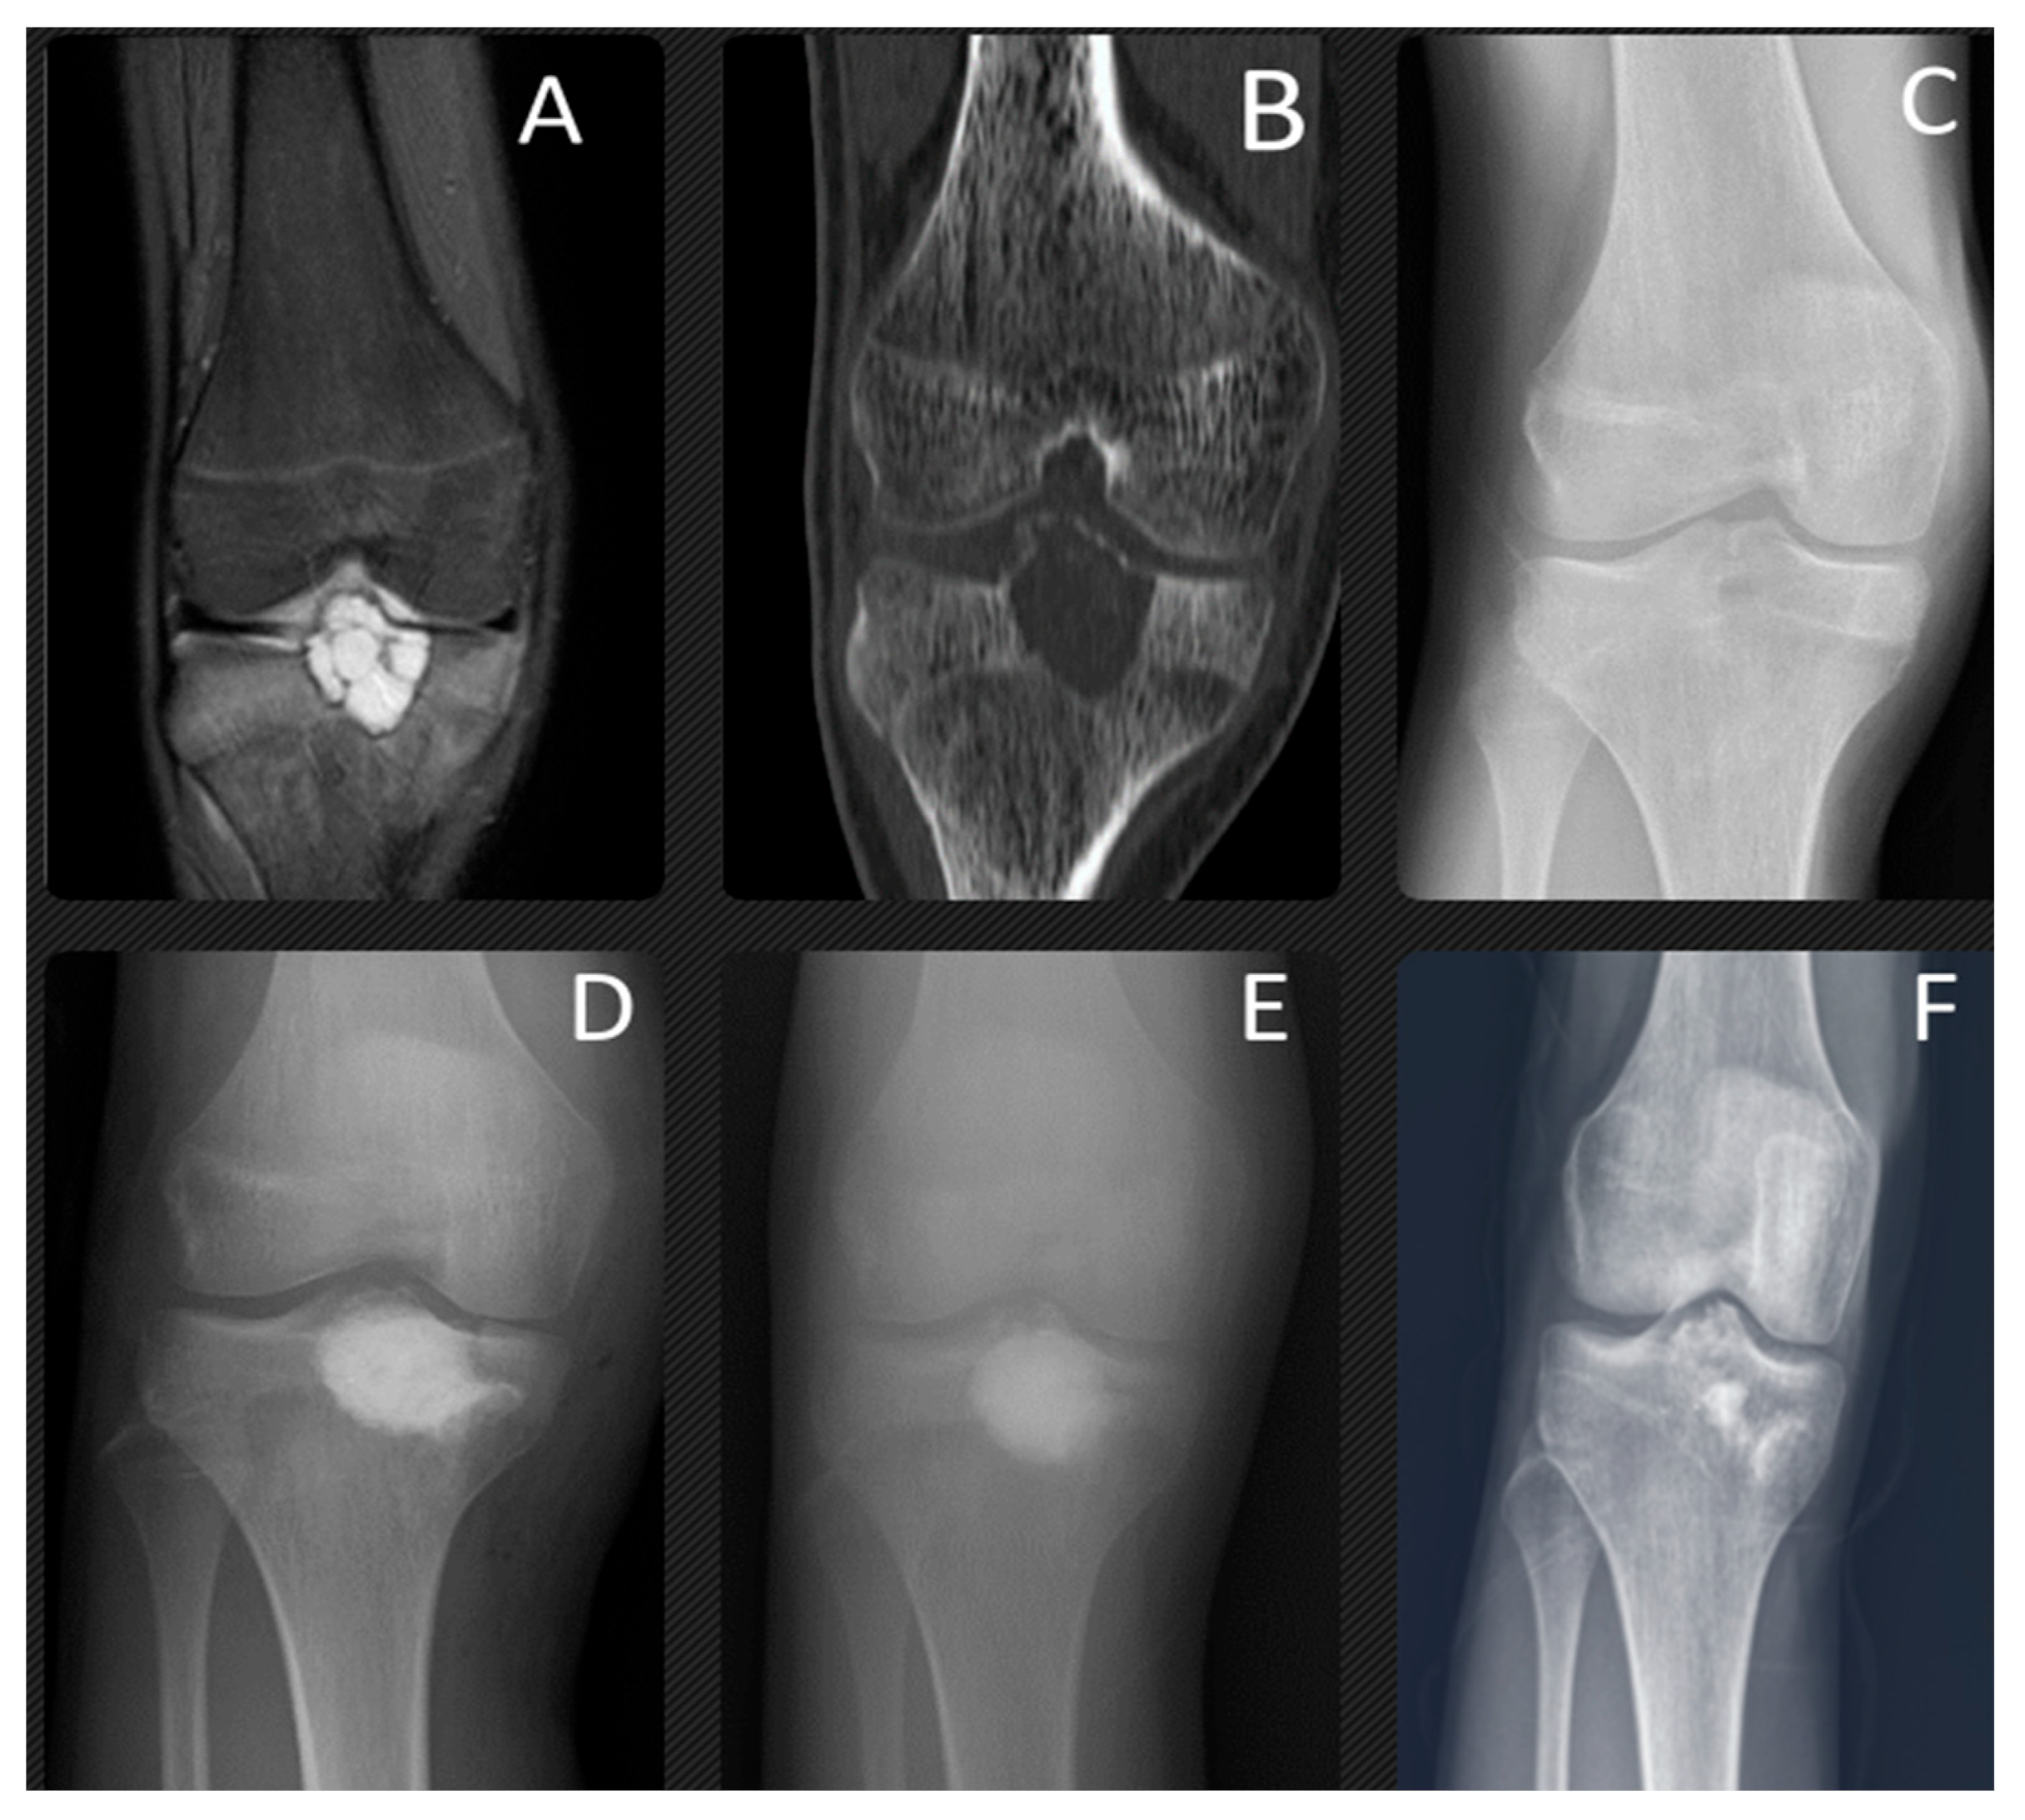

Figure 1. At the age of 17 years, this patient presented with chondroblastoma of the talus. A preoperative Tl-weighted (A) and T2-weighted (B) MRI, CT (C) and X-ray (D) radiograph showed a 3 cm lucent lesion within the talar neck. Expansile periosteal reaction was identified. In the distal part of the talus, particularly in the neck and the area near to the talonavicular joint, a microfracture was observed, along with considerable bone edema. This was treated with aggressive curettage and bone cementing. The final radiographs were taken 1 year (E) and 3 years (F) after surgery. Skeletal maturity shows the lesion had completely healed.